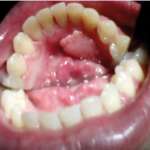

Caratteristiche cliniche ed epidemiologiche del fibroma traumatico orale

Una lesione del cavo orale piuttosto frequente nella pratica clinica odontoiatrica: una mini review valuta la letteratura degli ultimi anni per chiarire le caratteristiche di questa neoformazione, con particolare riferimento agli aspetti clinici ed epidemiologici.